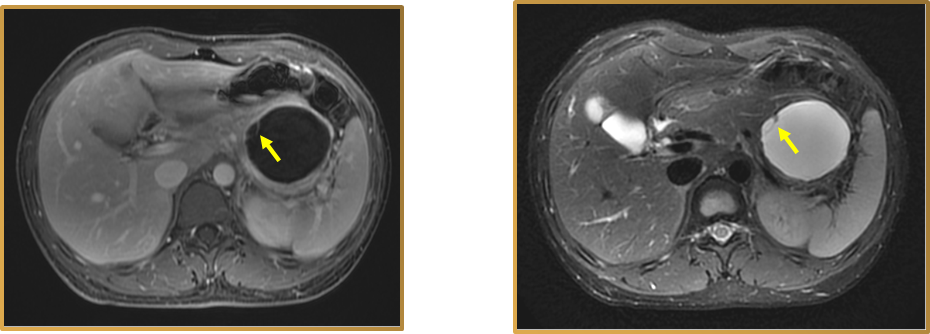

1. 双管征

即胆总管和胰管同时扩张,非常致命。提示胰头占位,主要见于胰头癌。

图11 胰头癌 双管征

(图片来源:余日胜教授讲课使用)